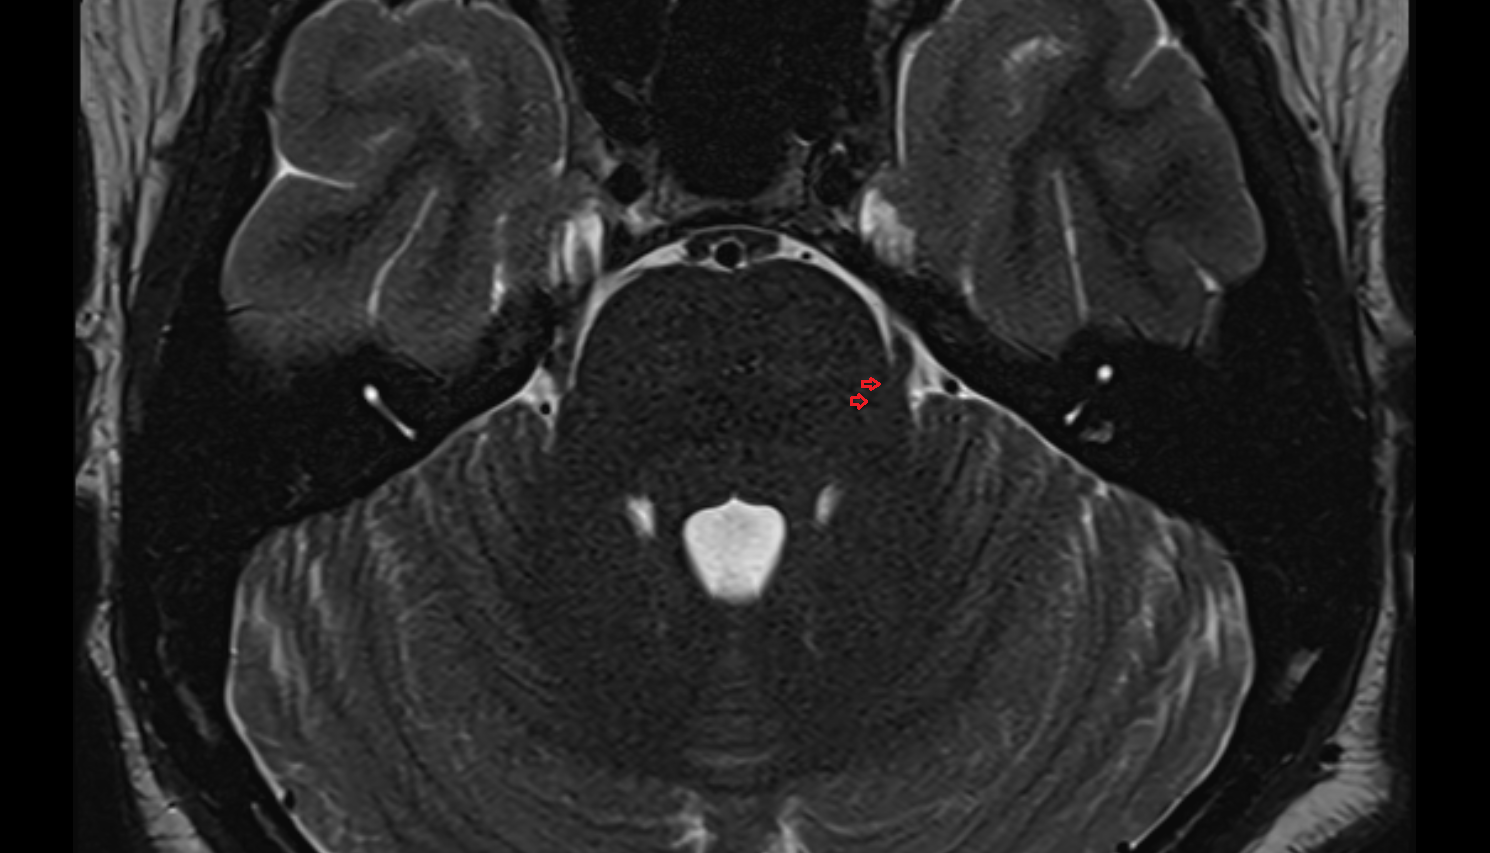

- Pons

- Cerebellopontine cistern

- Pontocerebellar cistern